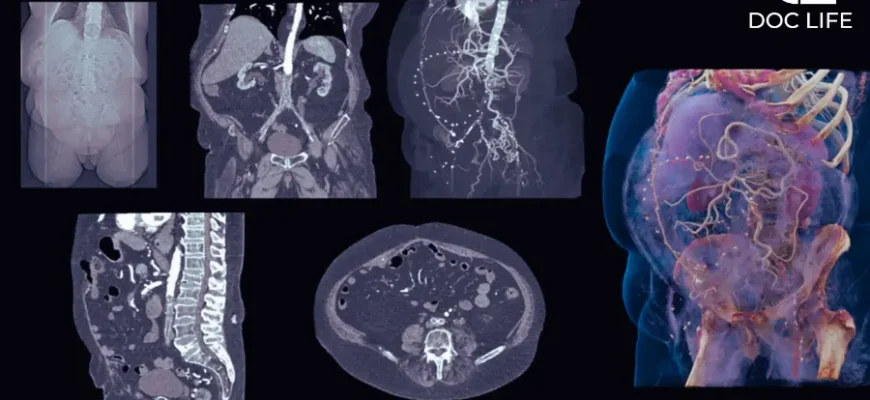

Ось суть: іноді лікарі додають контрастну речовину, щоб підсвітити певні тканини або судини. Це робить зображення чіткішими. Але чи завжди це потрібно? Не зовсім.

Тут нюанси. Контраст часто використовують для:

- Оцінка пухлин: Розрізнення доброякісних та злоякісних утворень.

- Становлення аномалій судин: Виразніше виділення кровотоку.

- Деталізація запальних процесів: Покращення видимості змін у тканинах.